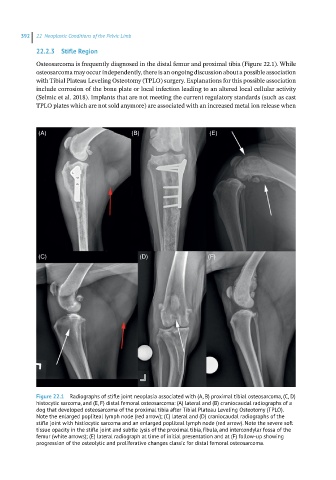

Figure 22.1 Radiographs of stifle joint neoplasia associated with (A, B) proximal tibial osteosarcoma, (C, D)

histocytic sarcoma, and (E, F) distal femoral osteosarcoma: (A) lateral and (B) craniocaudal radiographs of a

dog that developed osteosarcoma of the proximal tibia after Tibial Plateau Leveling Osteotomy (TPLO).

Note the enlarged popliteal lymph node (red arrow); (C) lateral and (D) craniocaudal radiographs of the

stifle joint with histiocytic sarcoma and an enlarged popliteal lymph node (red arrow). Note the severe soft

tissue opacity in the stifle joint and subtle lysis of the proximal tibia, fibula, and intercondylar fossa of the

femur (white arrows); (E) lateral radiograph at time of initial presentation and at (F) follow-up showing

progression of the osteolytic and proliferative changes classic for distal femoral osteosarcoma.